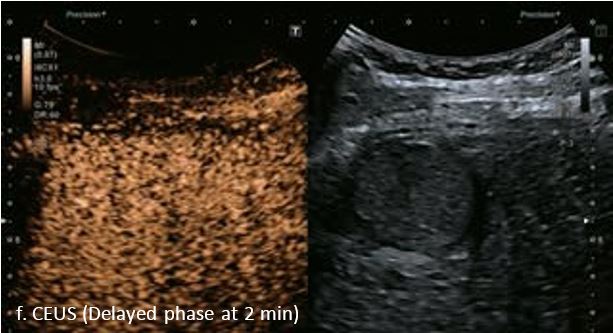

LI-RADS 5 ГЦК

У 63-річної жінки з алкогольним цирозом печінки виявлено ураження печінки розміром 3 см. Межа ізоехогенного ураження та його гіпоехогенний ореол може бути чітко відображений на сірошкальному зображенні. За допомогою кольорового доплера можна виявити внутрішньопухлинну судинну структуру. Багата судинна структура може бути окреслена за допомогою SMI, та можуть бути показані викривлені судини, що свідчить про злоякісне ураження. Після ін'єкції контрасту, в артеріальній фазі, ураження демонструє гомогенне гіперпосилення, пов'язане з підживлюючими судинами. Вимивання не спостерігається на 1 хвилині і на 2 хвилині. У відстроченій фазі на 3,5 хвилині можна спостерігати помірне вимивання. Вимивання повільно прогресує і стає більш чітким на 5 хвилині. Пізнє (≥ 60 сек) і помірне вимивання є однією з основних ознак LI-RADS 5 і є дуже важливим для диференціації від LI-RADS M, який показує раннє (<60 сек) і/або виражене вимивання. В результаті ураження класифікується як CEUS LI-RADS 5. Класифікація CEUS LI-RADS відповідає LI-RADS на КТ.

Малюнок 9